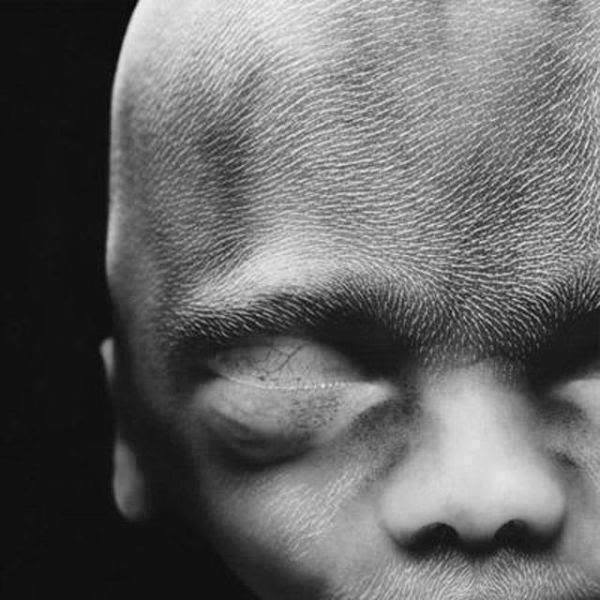

14. 到了第10週左右時,胎兒的眼臉已經發展出來,只是還沒有辦法完全閉合。

16.這時胎兒的骨骼都是由軟骨所構成的,我們能夠從薄薄的皮膚當中,清楚看到血管的分佈。

17. 懷孕18週,胎兒大小大約有14公分,這時他們也可以聽到外界的聲音啦!